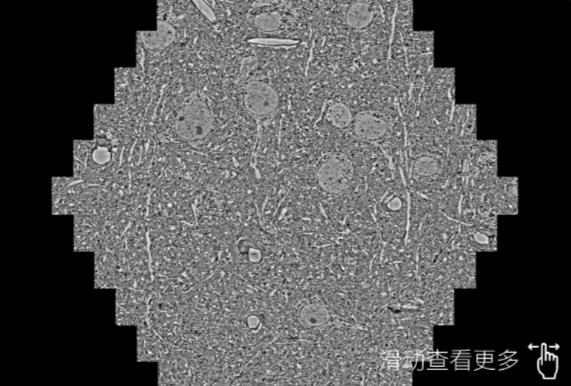

鼠脑切片。左图使用沙坪坝蔡司沙坪坝扫描电镜MultiSEM706对165μmx143pm面积区域成像,耗时仅需1.5秒。右图为鼠脑切片中30μm区域放大效果。样品由芝加哥大学B.Kasthuri提供。

使用蔡司高速沙坪坝扫描电镜MultiSEM对1mm²人脑皮层组织进行高分辨成像,并对其中的各种细胞结构进行三维重构分析。左图展示了2x3mm²组织平面中锥体神经元的三维重构效果。右图显示了局部体积神经元三维重构。图像由哈佛大学chtman实验室提供,渲染图由D. Berger 制作。